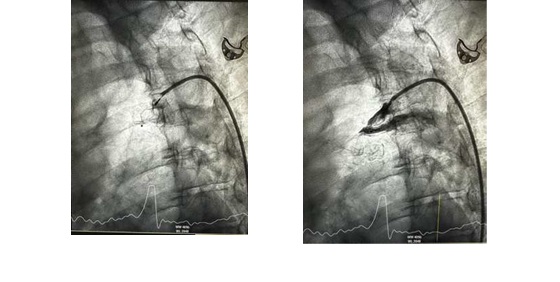

Ακτινοσκοπικές λήψεις από την τοποθέτηση της συσκευής σύγκλεισης του Βοτάλειου Πόρου και η επιβεβαίωση της πλήρους σύγκλεισης μετά από χορήγηση σκιαστικού.